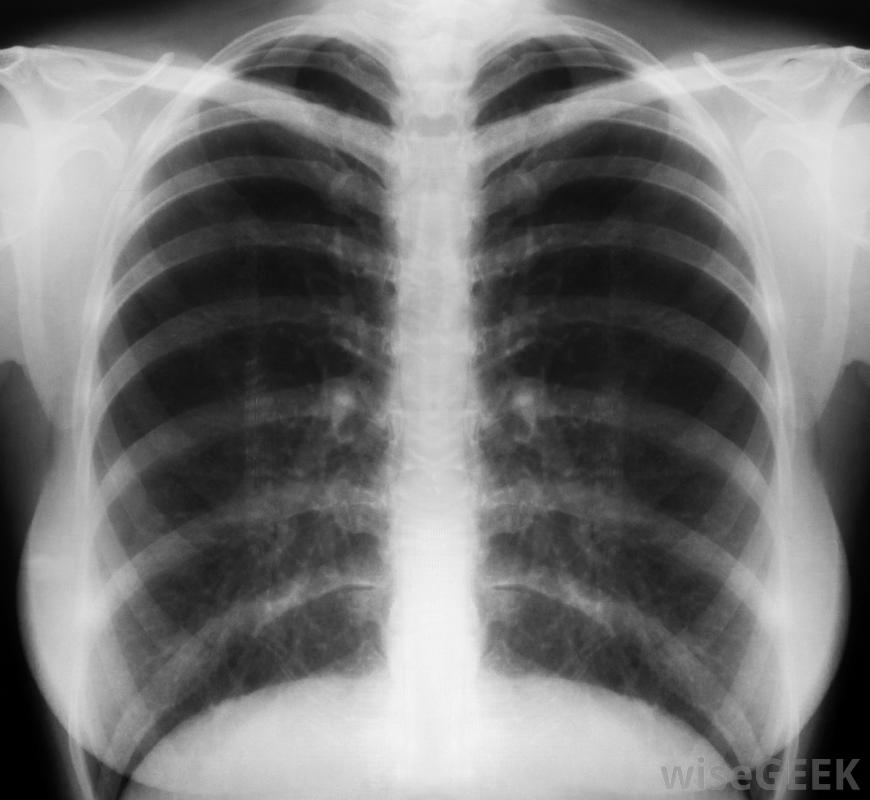

,毛細支氣管炎是支氣管內膜的炎癥,細支氣管炎是細支氣管或肺部小通道的炎癥。這種病毒感染在秋季和冬季會影響兒童和嬰兒。雖然通常不需要治療,但在孩子病情嚴重的情況下,可以服用抗病毒藥物。患有毛細支氣管炎的兒童可能會出現發燒、喘息或呼吸急促的癥狀。通常通過檢測患兒的鼻液和進行胸部x光檢查來確認診斷。

與其他呼吸系統疾病一樣,肺炎是由肺部炎癥引起的。呼吸急促、發熱和咳嗽等癥狀都可以作為肺炎的征兆。診斷可通過多種檢查來進行,包括全血細胞計數(CBC)、胸部CT掃描和痰培養試驗,嚴重咳嗽時排出的粘液樣物質。一些肺炎需要住院治療,而較輕的病例可能只需要使用抗生素。

SARS患者可能會出現嘔吐等癥狀,腹瀉、流鼻涕和喉嚨痛。用于診斷SARS的檢查包括胸部CT掃描、全血細胞計數(CBC)和胸部x光片。SARS的治療包括隔離住院、使用抗生素和抗病毒藥物以及類固醇以減少肺部炎癥。嚴重者,除了機械通氣或人工呼吸支持外,還可使用氧氣。與SARS相關的并發癥包括呼吸、心臟和,呼吸急促是冠狀病毒引起肺炎的指標。